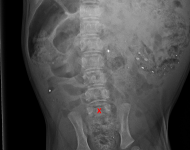

MVDr. Meloun: Lumbosakrální přechodový obratel